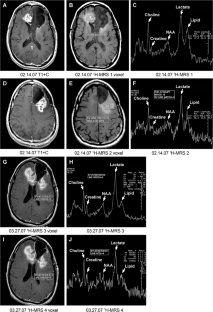

Fig. 1

Fig. 2

Fig. 3